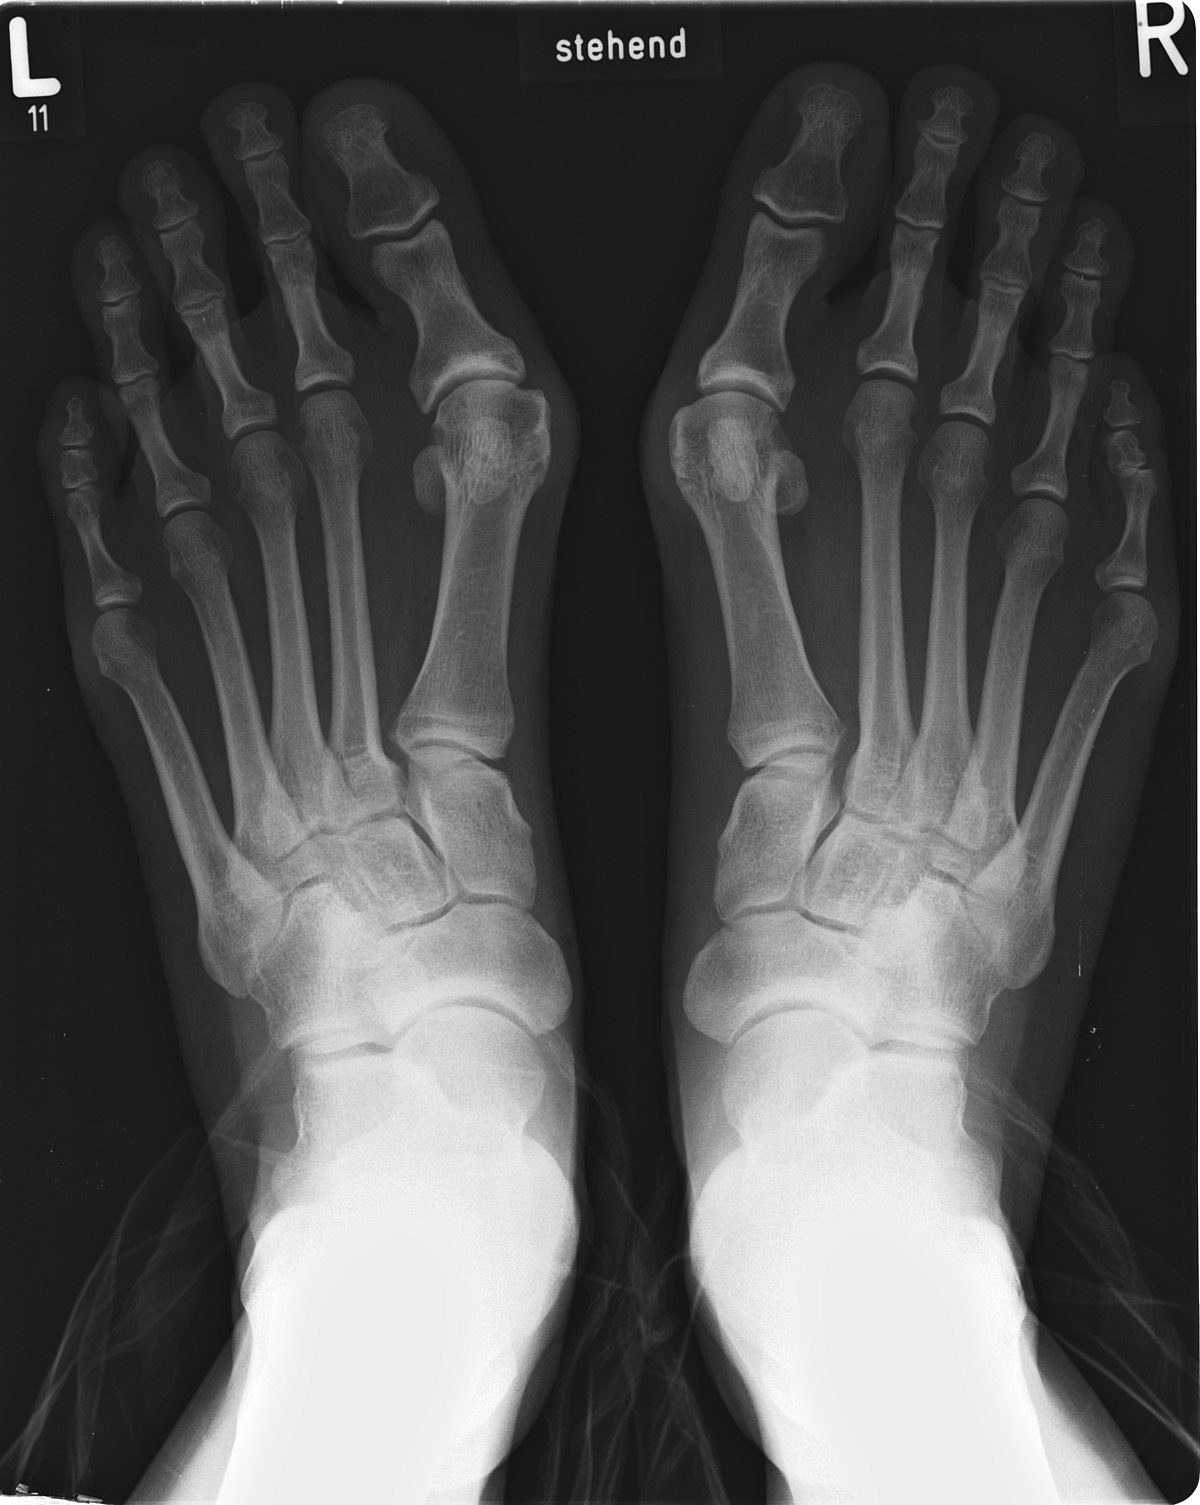

주로 중년 여성분들에게서 많이 생기는 질환입니다. 여러가지 병인이 있겠지만 주로 신는 좁은 신발들의 변형으로 생기며 유전적인 원인 및 긴 엄지발가락이 원인될 수 있습니다. 편평족이나, 종자뼈가 바깥쪽 아탈구가 있는 경우 '무지외반증' 이 진행되기도 합니다.

이러한 변형 자체는 크게 문제가 없으나, 변형으로 인해 계속되는 중족골 원위부 내측의 마찰로 인하여 굳은살이 생기고

심한경우 엄지발가락이 두번째 발가락을 침범하게 됩니다.

일단 치료 방식을 결정하기 전에, 엑스레이로 '무지외반증' 정도를 평가합니다.

기본 엑스레이를 통해 각도를 측정하는데 동일한 AP view 에서 주로 평가합니다.